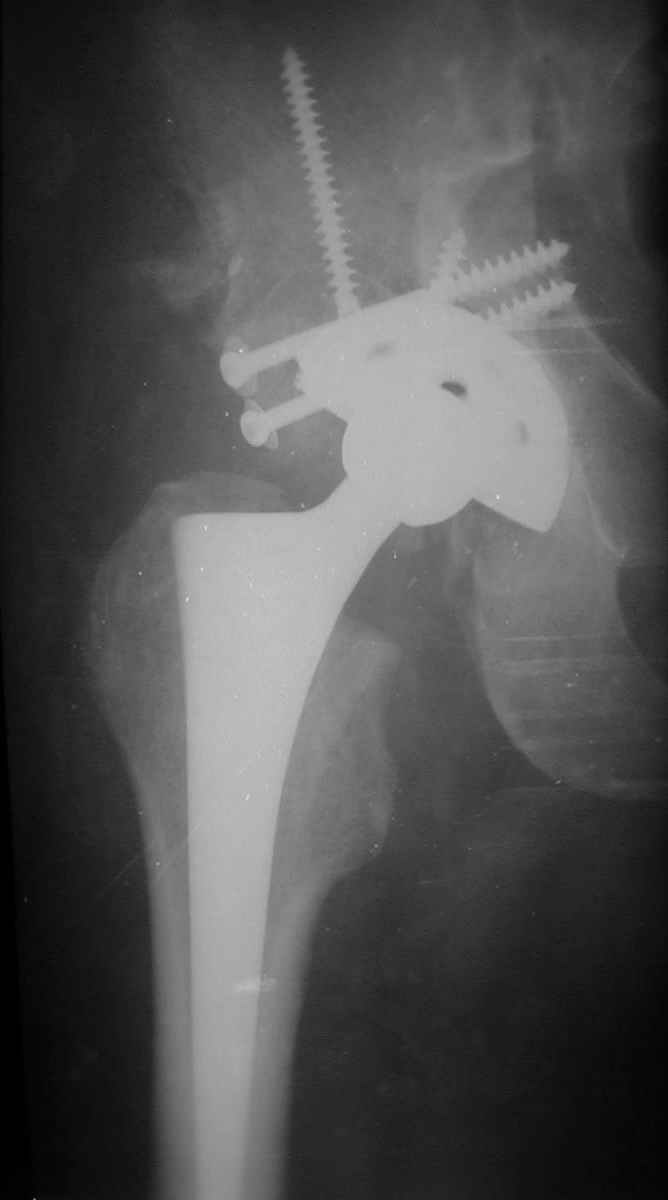

В институте совместно с фирмой Зиммер достаточно регулярно (практически ежемесячно) проводятся 2-х недельные циклы по различным вопросам эндопротезирования. Если есть возможность и желание, мы готовы поделиться с Вами нашим опытом, тем более есть что показать и что обсудить - в настоящее время ежедневно выполняется от 6 до 10 эндопротезирований коленного и тазобедренного сустава. В качестве примеров хочу показать 2 наблюдения, через 1 год и 5 лет после операции

1 год